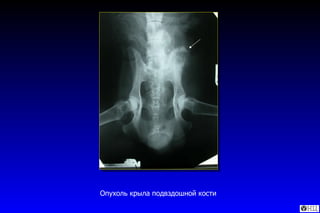

Опухоль крыла подвздошной кости

Мелкоклеточная остеосаркома, гематоксилин-эозин,  х10